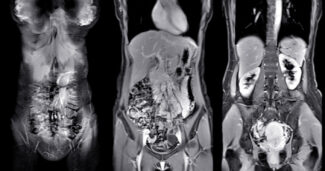

Magnetic Resonance Imaging (MRI) is often recommended to help detect, diagnose, and monitor tumors in the chest, abdomen, or pelvis. MRI provides detailed images that assist physicians in evaluating these areas with accuracy and without exposing patients to radiation. Contact Greater Waterbury Imaging Center to schedule your MRI today.

MRI for Tumors of the Chest, Abdomen, or Pelvis

MRI is often chosen because of its ability to generate high-resolution, multiplanar images of soft tissues. Unlike CT scans, MRI does not use ionizing radiation, which can be especially important for patients requiring repeated follow-up imaging.

Compared to other modalities, MRI offers superior contrast resolution for many tumors. For example, it can better differentiate liver lesions, characterize pelvic masses, and evaluate mediastinal or chest wall tumors. In some cases, MRI is used in conjunction with CT, PET, or ultrasound to provide a comprehensive diagnostic picture.